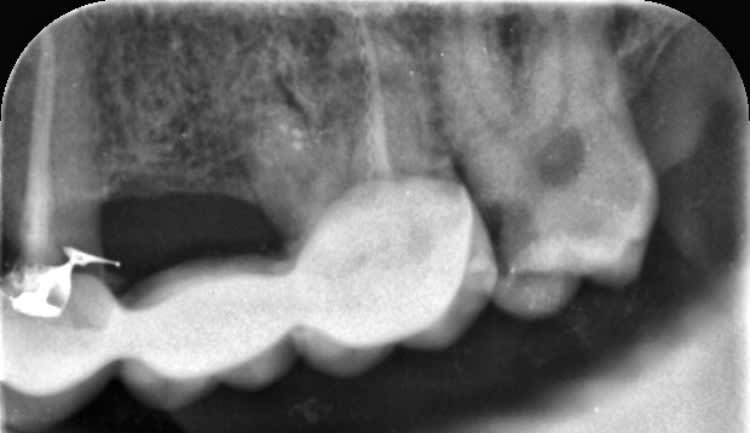

Oui toujours pas trouvé le moyen de trouver le mv2 et d'obturer les 4 canaux en 15 minutes. Caramba que 3 encore raté. Des solutions ?

Là, la solution c'était un microscope opératoire, un insert US multilames style CAP3 de chez satelec, une lime 8 et du temps... surtout du temps ! Mais au vu de ta photo, je suis presque sûr qu'il y en a un qui se cache !

Il y en a toujours un mais pas au tarif sécu de merde.

P4D EMS. En loupes fois 5 que dalle. Solution cone beam pour éviter de friter toute la chambre en mésio vestibulaire.